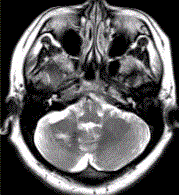

问题 患者女,41岁。头痛半年,加重10d。头部MRI显示如下图。 可能的诊断是(提示MR增强检查如下图。)

选项 A.海绵状血管瘤 B.发育性静脉畸形 C.AVM D.毛细血管扩张症 E.动脉瘤 F.硬脑膜动静脉瘘 G.海绵状血管瘤伴发育性静脉畸形

答案 G